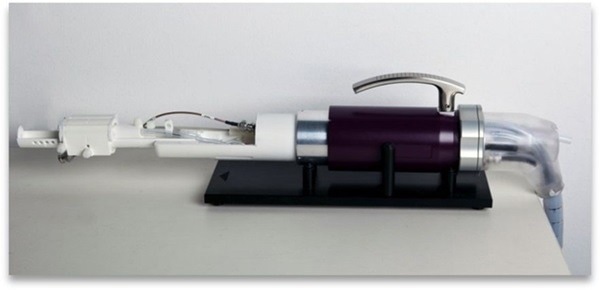

The animal handling system uses simple, fully integrated anesthetic, warmth, and physiological monitoring devices to keep the animal stable throughout the imaging session.

Animal handling system

Fully integrated animal handling and coil system includes:

Image Credit: Scintica Instrumentation Inc

- Beds suitable for a variety of sized animals such as mice, rats, and non-human primates

- Anatomy-specific coils improve signal-to-noise ratio and image quality

- Completely integrated anesthetic delivery and gas exhaust scavenging

- Individually controlled, multi-point, isoflurane vaporizer

- Continuous monitoring of the ECG, heart rate, respiratory rate, and body temperature

- Enables ECG and/or respiratory triggering

- To keep the body temperature stable, heated water is constantly circulated